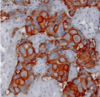

what is this condition?

what growth factor receptro is mutated in this condition?

ductal carcinoma

ERB B2 also referred to as (HER-2/Neu)